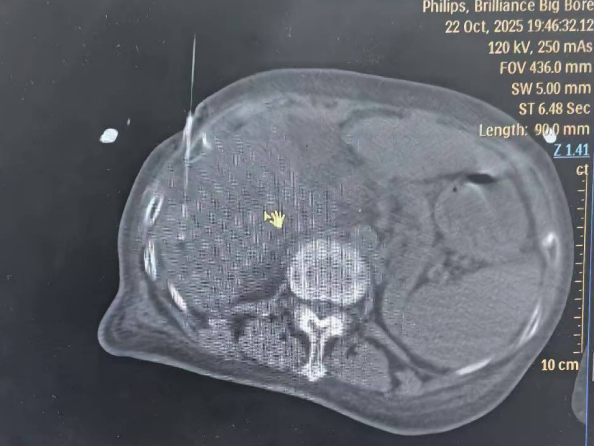

消融术中影像

术中,患者生命体征极度不稳定,血氧饱和度在70%至90%之间波动,呼吸急促导致消融针随膈肌大幅摆动,CT影像出现明显重影,为精准穿刺带来极大挑战。治疗过程中医生们沉着冷静、各司其职:麻醉科郭振海教授全程严密监护,精细调控呼吸与心率,确保能在血氧短暂回升至90%的宝贵窗口期内进针;陶冀教授团队则采取“阶梯功率、分次消融”策略,首轮以40-50-70W功率渐进消融9分钟后,调整针道进行第二循环治疗,最终完整覆盖两处紧贴肝被膜的病灶,肿瘤完全消融。历时2小时,手术顺利完成,患者未出现出血、气胸等并发症,术后生命体征逐步平稳,实现精准消融与安全治疗的双重目标。